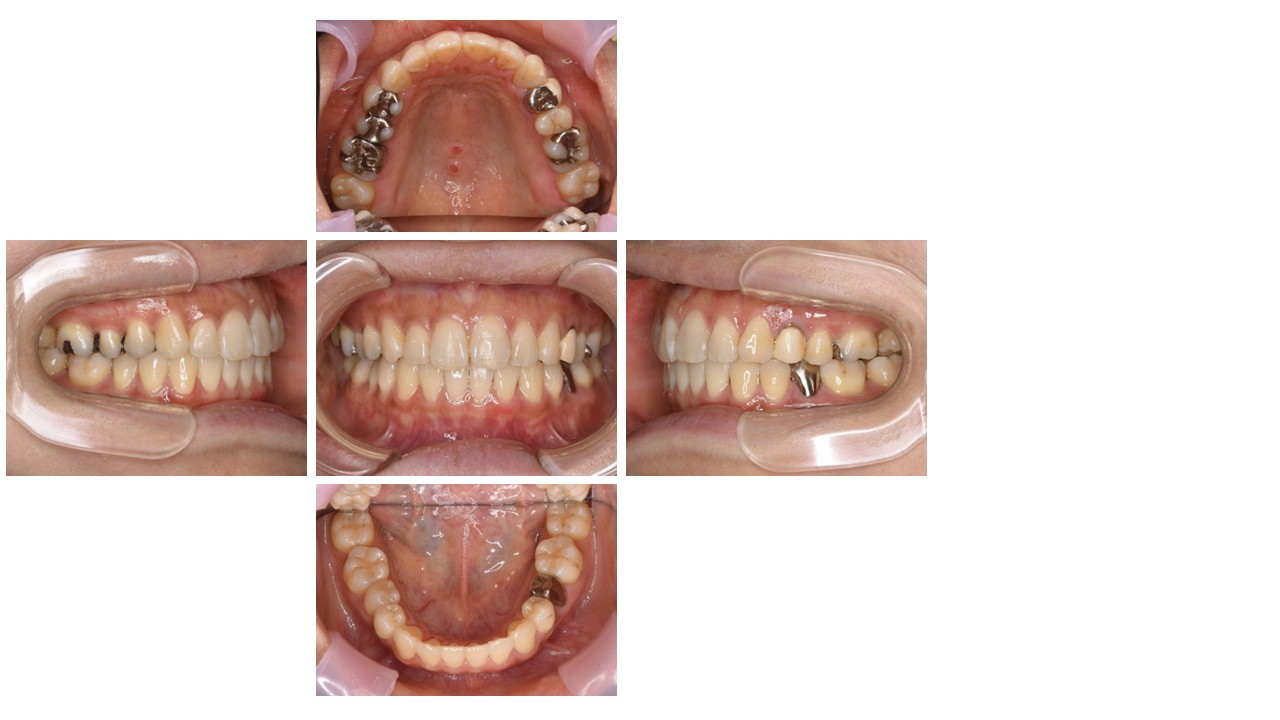

治療前